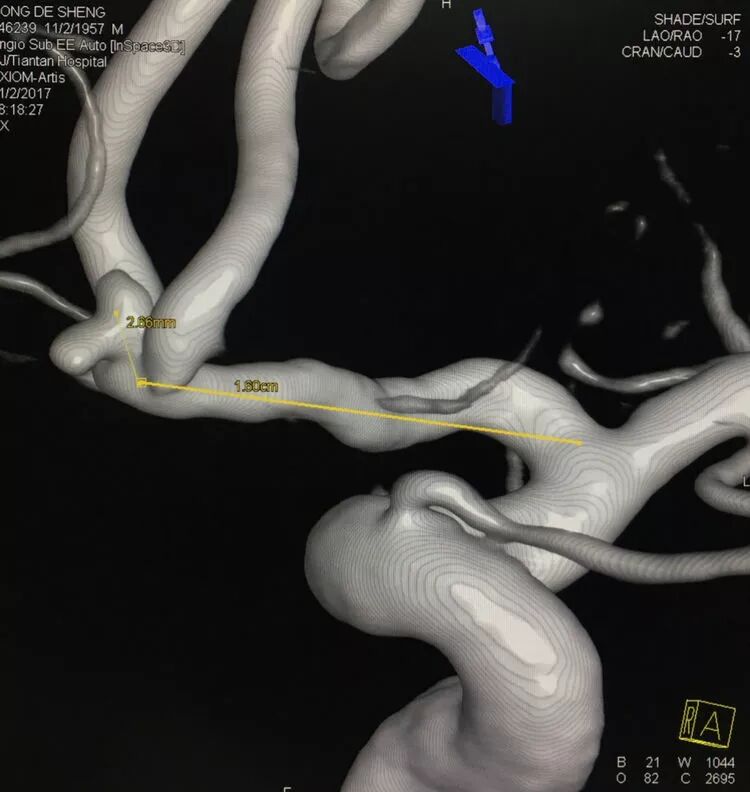

基底动脉顶端微小动脉瘤,是个有欺骗性的病例。从下面这个角度的造影看,瘤体长轴跟基底动脉主干平行,似乎用直头微导管栓塞即可

但从侧位造影和CTA观察,其实瘤体长轴还是跟基底动脉主干有成角的。这家医院的DSA机器没有三维重建工作站,只能参考CTA

于是我们把微导管头塑成S形

顺利完成该动脉瘤的栓塞。所以,要多角度观察动脉瘤跟载瘤动脉的解剖走行,即使硬件上没有三维工作站,咱们头脑中也要有立体构象,不要一叶障目,被狡猾的敌人所欺骗